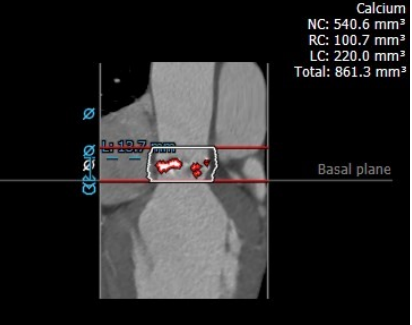

钙化评估

根据术前评估为type2二叶瓣,极重度钙化,左右窦左无窦有钙化粘连,窦部较小,术中需要囊扩张确认冠脉情况。考虑到瓣上结构瓣膜预选L29,直径满足要求,主动脉弓锐角,术中过弓谨慎。